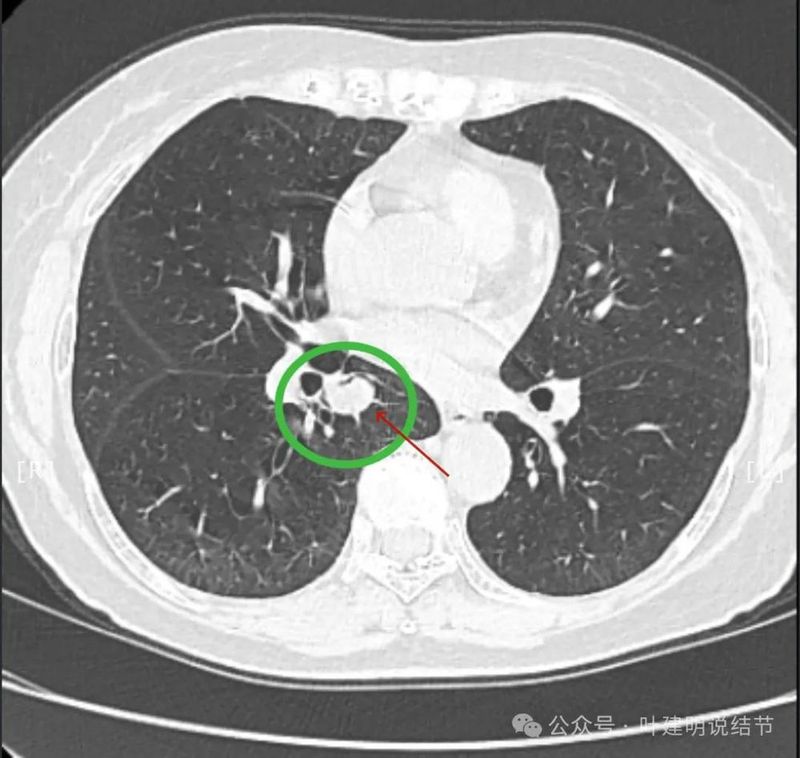

再看2024年5月时复查的影像:

分叶,混合偏实性密度,血管贴边走行。

与支气管紧贴,黄色箭头所示处似乎支气管壁与病灶已经愈着。

上图又见结节与支气管不是都愈着的,说明侵袭性并不强,病灶表面光滑。

天蓝色箭头所指处是北段支气管与病灶之间,感觉较2月份贴得近了一点点。病灶表面仍是光滑的,总体感觉有膨胀性。

病灶边缘光滑,有血管穿出来似的。

表面光滑,有膨胀性。